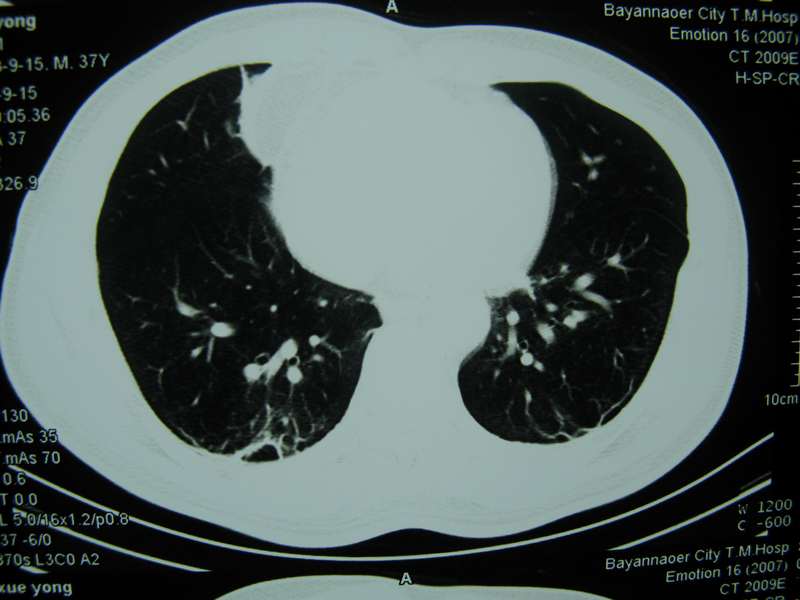

男,37岁,主述胸疼厉害,无咳嗽,无发热,血象也不高,病灶内ct值脂肪密度,右侧胸腔内少量积液,同道们考虑什么?谢谢!

两肺下叶基底段纤维灶,右肺下叶基底背侧相应胸膜肥厚,右肺中叶内侧段部分不张。前中下纵隔团块状脂肪影,随访除外胸腺脂肪瘤。